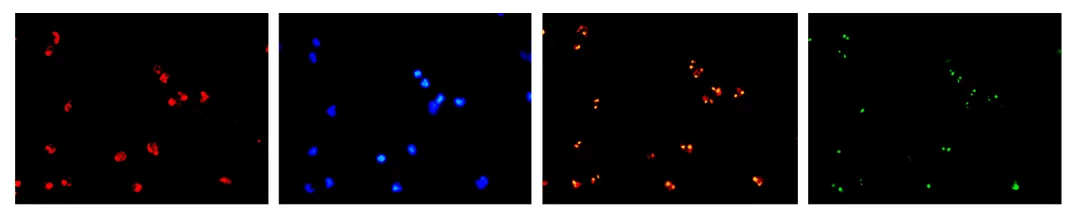

Ã÷ÃĀÉúÎīī@ÎĸįR´îÅämsx2ÅÄzHEČžÉĢĩÄČéĪŲ°Š˛ĄĀíĮĐÆŦŖŦŧtÉĢé°ûŲ|ŖŦË{ÉĢéČžÉĢķw

MF43-N+MC50-S´îÅäËIJ¨ļΚâÔ´ÅÄzĩÄFISHDĪņ